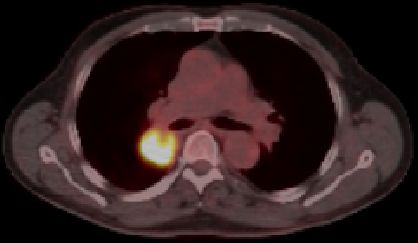

blauer Punkt   56-jähriger Mann mit einem Adeno-Ca des rechten Mittellappens. Im CT große Raumforderung im rechten Hilus. Das PET-CT zeigt, dass der eigentliche Tumor unterhalb der Raumforderung sitzt.